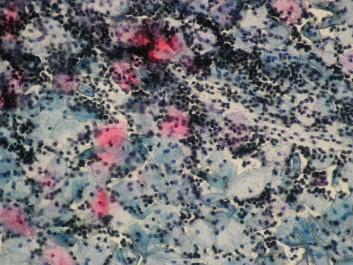

• ​